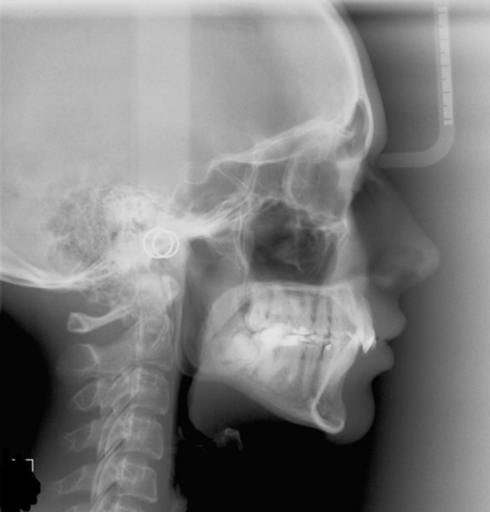

Overjet? Braces? Is my upper jaw forward or my lower jaw back??

I am 26 yr old female and i have finally gathered the money to get my braces done. Over the years i have been told that my lower jaw is "pushed back" and it could cause problems when am older. The last orthodontist i went to, mentioned that i have...